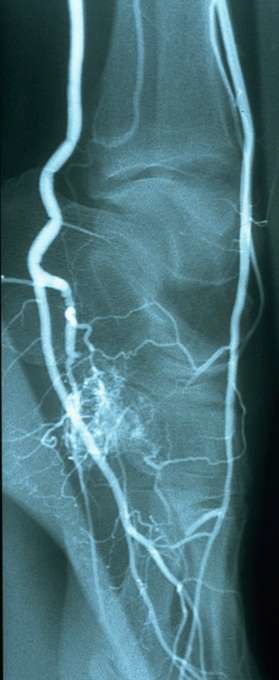

动静脉畸形在不同的部位可能的生理病理影响是不一样的。在肢体部位由于大量的动脉血经瘘口回流导致肢体远端缺血和静脉高压。栓塞瘘口可以改善远端动脉血流的灌注,改善缺血状态。 33岁,男;足趾溃疡。发现足动静脉畸形。

TYPE II